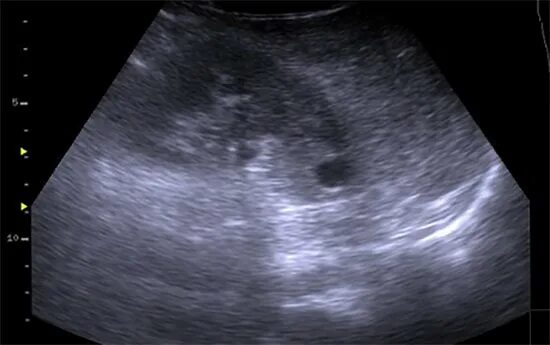

Анэхогенное включение неправильной формы